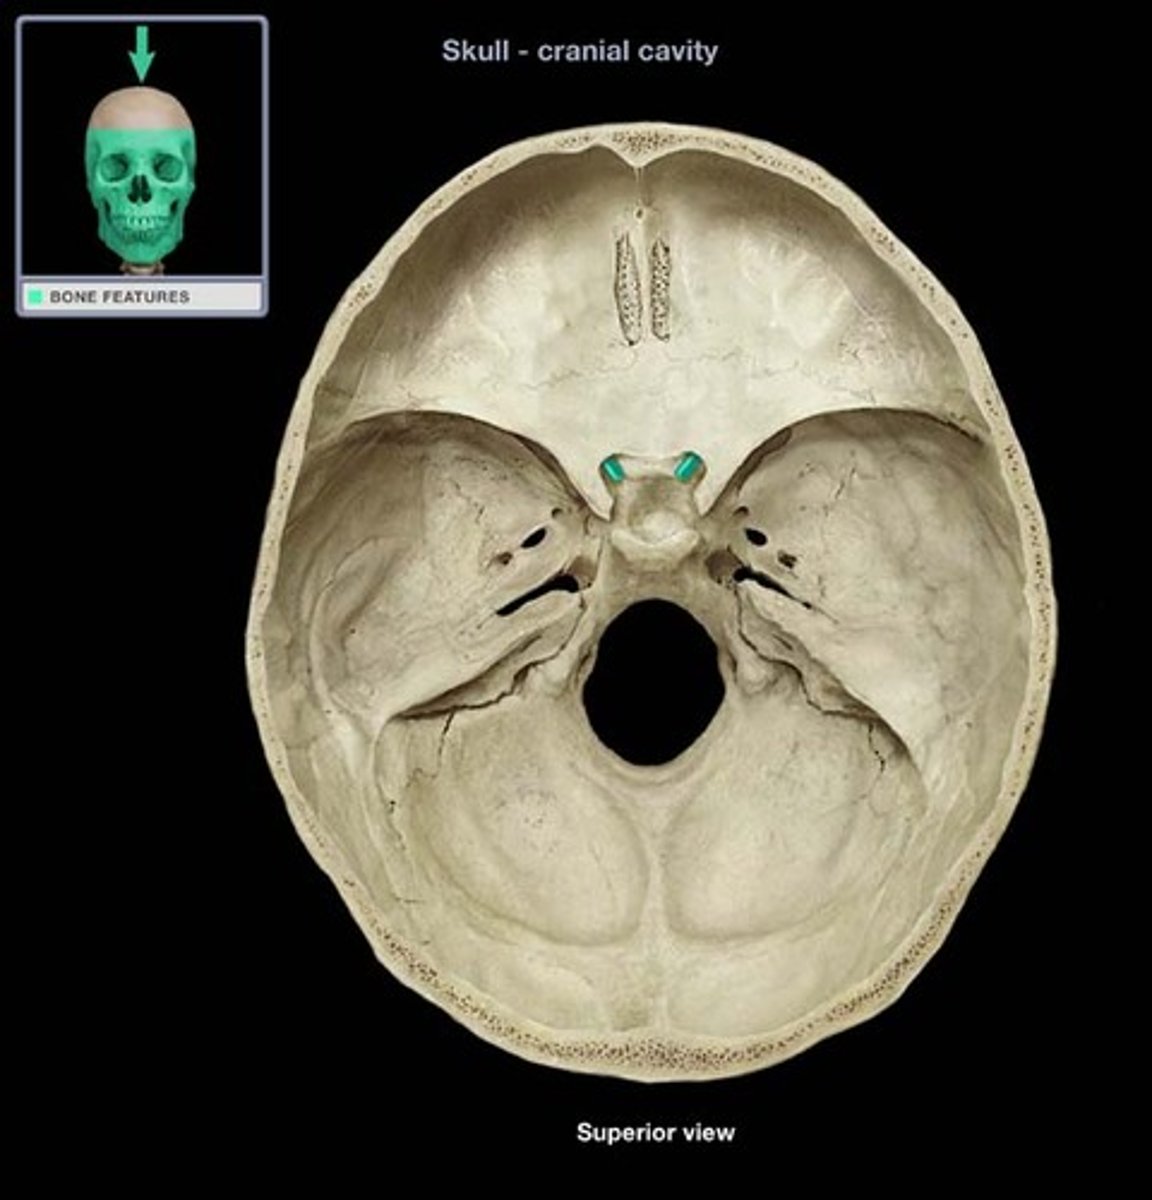

Optic Foramen/Canal